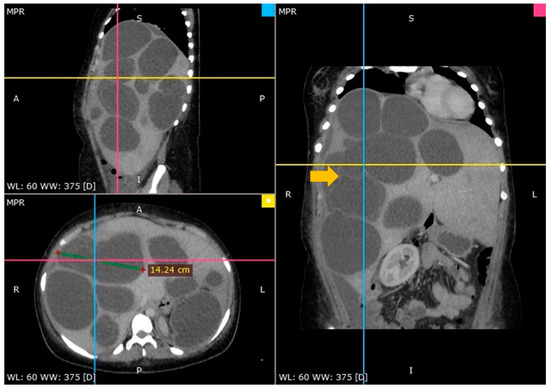

3.1. Case 1

3.2. Case 2